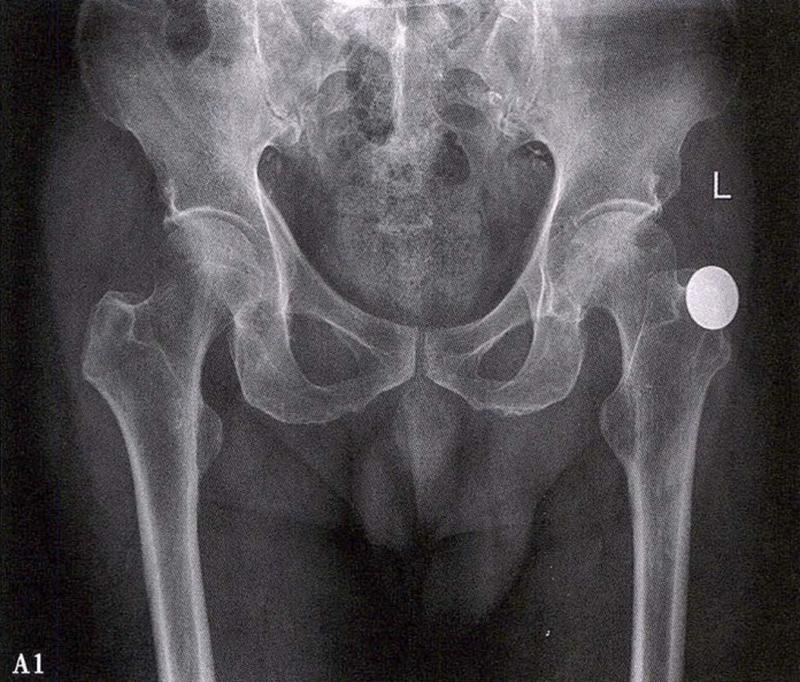

A.男性,71岁,双侧股骨头坏死,右侧Ⅰ期、左侧Ⅲ期。X线片示双侧股骨头形态可,右股骨头未见明显密度改变,左股骨头关节面下见局限性骨密度减低及增高区(A1)。MRI(T2加权像)示右股骨头内双线征,左侧不规则形混杂信号,坏死区远端骨髓水肿(A2、A3)。